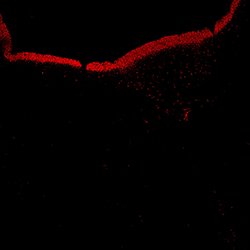

KI67

6PCW human midbrain